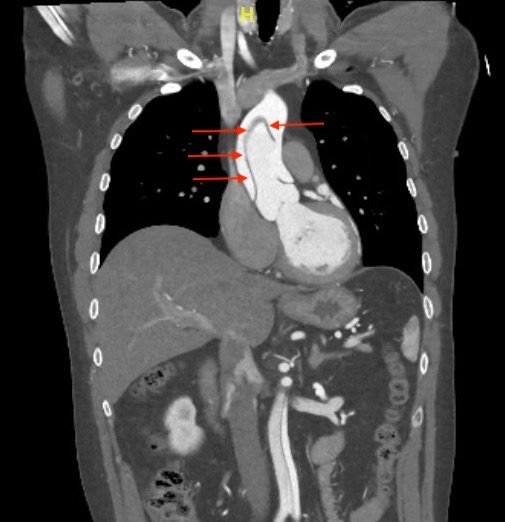

We present a case of a 51-year-old previously healthy man who presented to the ED complaining of chest pain that had resolved prior to arrival, and a mild headache. His vital signs were notable for hypotension, but physical exam was unremarkable. Chest x-ray revealed a borderline widened mediastinum. A standard ETTE was within normal limits, but additional SSNV demonstrated a dissection flap in the aortic arch. The patient was taken to the operating room for surgical repair 75 minutes after the ED ultrasound was performed; the operation was successful, and the patient was discharged to home post-operatively with good outcome.